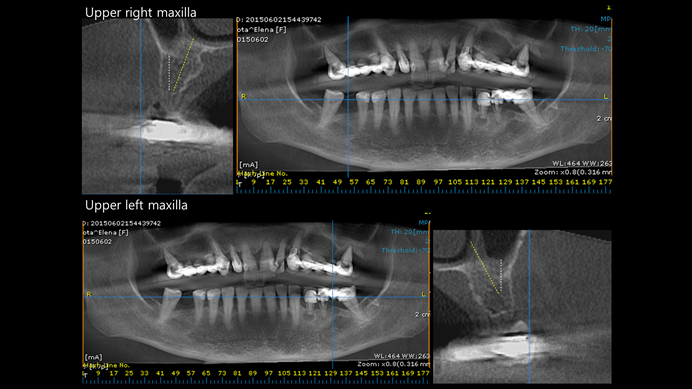

Keywords

AnyRidge, immediate placement, immediate provisionalization, maxillary fully edentulous case, initial stability, edentulous, Dr. Iulian Filipov, R2GATE, MEGA ISQ

Products:

AnyRidge implant system, Mega ISQ, R2GATE